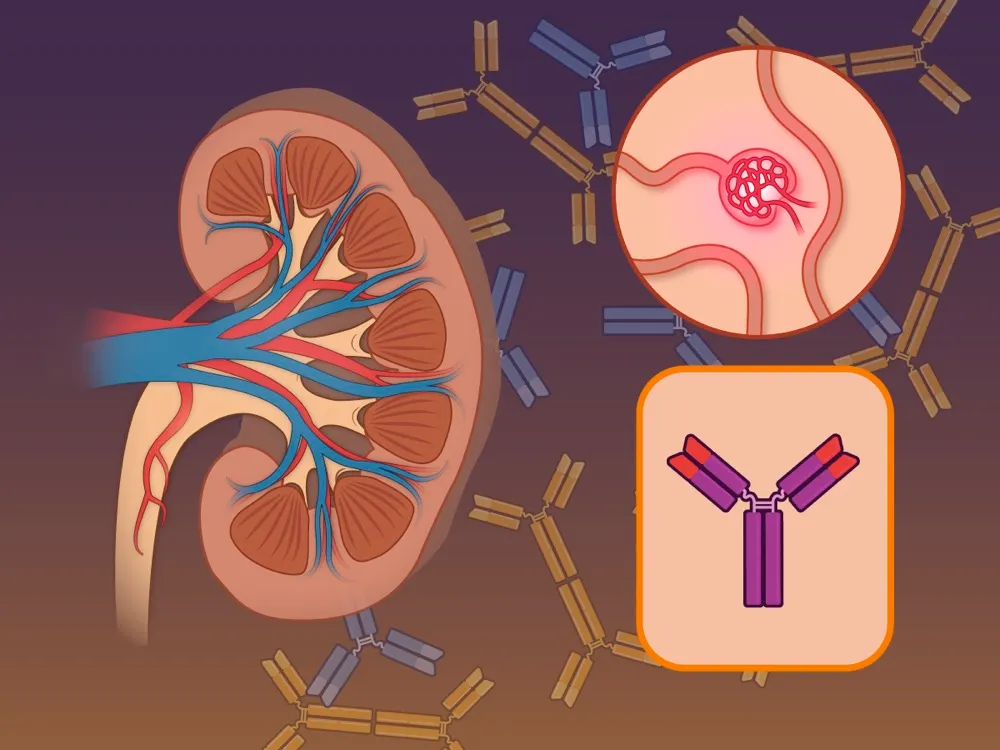

A DRPAD não é contraindicação à DP — e, na prática, muitos pacientes têm resultados comparáveis à hemodiálise. O “porém” está na mecânica: rins/hepatomegalia podem reduzir tolerância a volumes, aumentar risco de hérnias e extravasamentos, e piorar desconforto respiratório. Com técnica adequada (cateter presternal ou lateral, volumes menores, cicladora noturna e decúbito supino), a maioria das barreiras é contornável. Neste post, revisamos quando a DP é ótima, quando exigir cautela e como ajustar a prescrição para segurança e qualidade de vida.